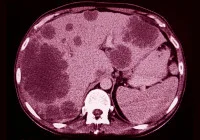

Accurate preoperative assessment of ovarian cancer spread is crucial for determining tumour resectability and guiding treatment strategies. While contrast-enhanced computed tomography and magnetic resonance imaging remain standard diagnostic tools, ultrasound is gaining prominence for its real-time imaging capabilities and accessibility. A recent study published in Ultrasound in Obstetrics & Gynecology evaluated the accuracy and consistency of ultrasound examiners—ranging from less experienced to highly experienced—in detecting cancer infiltration across defined anatomical regions using preacquired videoclips. By examining diagnostic confidence, image quality and inter-rater agreement, the study sought to determine the viability of ultrasound in advanced cancer staging when operated by differently skilled clinicians.

The study formed part of the Imaging Study in Advanced Ovarian Cancer (ISAAC) and focused on a secondary aim: evaluating the ability of ultrasound raters to detect cancer spread using 380 pre-recorded videoclips. These clips were obtained from 96 patients with a high prevalence of ovarian cancer spread, covering 19 anatomical sites grouped into four regions: pelvis, middle abdomen, upper abdomen and lymph nodes. Sites critical for assessing tumour resectability were also specifically included. Each anatomical site featured ten clips with and ten without visible cancer infiltration, judged against surgical, histological or treatment response findings.